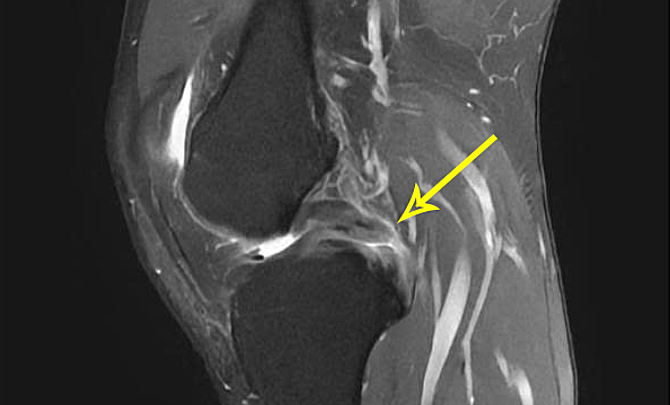

Bác sĩ Nghĩa phát hiện xương chày anh Giang tụt ra sau so với đùi, chỉ định chụp cộng hưởng từ MRI ghi nhận dây chằng chéo sau mất hoàn toàn tín hiệu. Bác sĩ chẩn đoán bệnh nhân đứt hoàn toàn dây chằng chéo sau độ ba.

Thông thường, đứt dây chằng chéo sau có thể điều trị bằng cách nghỉ ngơi, nẹp bất động gối. Bệnh nhân đi nạng để kiêng vận động khoảng 6 tuần có thể giúp dây chằng chéo sau tự lành. Song anh Giang phát hiện tổn thương quá muộn, không kiêng vận động vì không thấy đau nên dây chằng chéo sau đã đứt hoàn toàn, kèm rách sụn chêm. Bệnh nhân trẻ tuổi, nhu cầu vận động cao nên phải phẫu thuật để khôi phục hiệu quả chức năng khớp gối.

Phim MRI cho thấy dây chằng chéo sau của anh Giang đứt hoàn toàn. Ảnh: Bệnh viện Đa khoa Tâm Anh